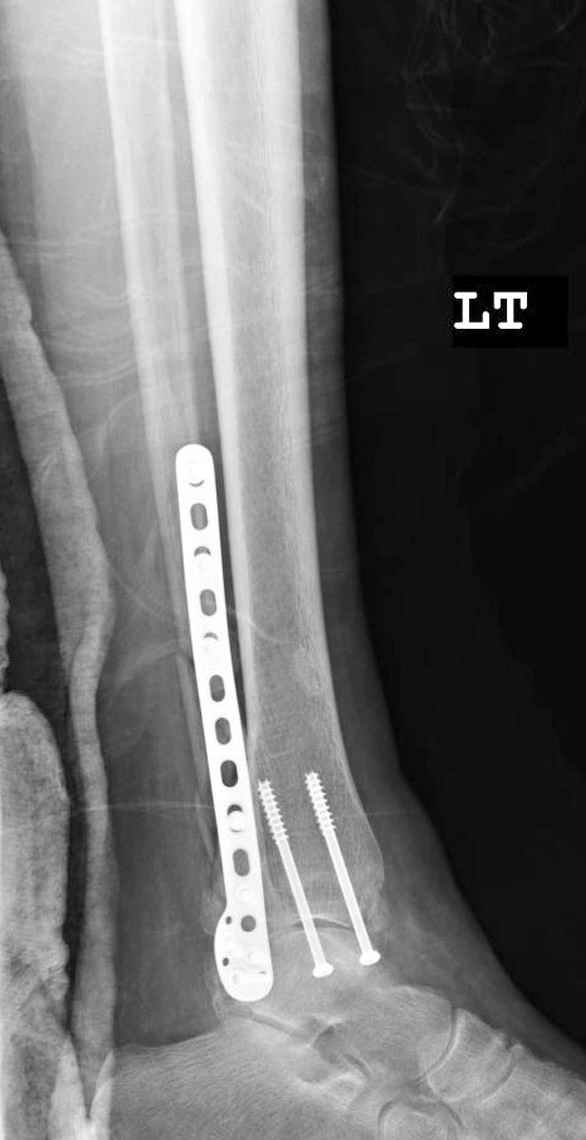

Малоберцовая выглядит коротковатой. Профиль как-то мутный. Вообще, неплохо было бы сделать снимки в сравнении со здоровой.

> Малоберцовая выглядит коротковатой. Профиль как-то мутный.

Конечно, малоберцовая укорочена, надо сделать косой - мортиз снимок, тогда будеть понятно, на сколько.